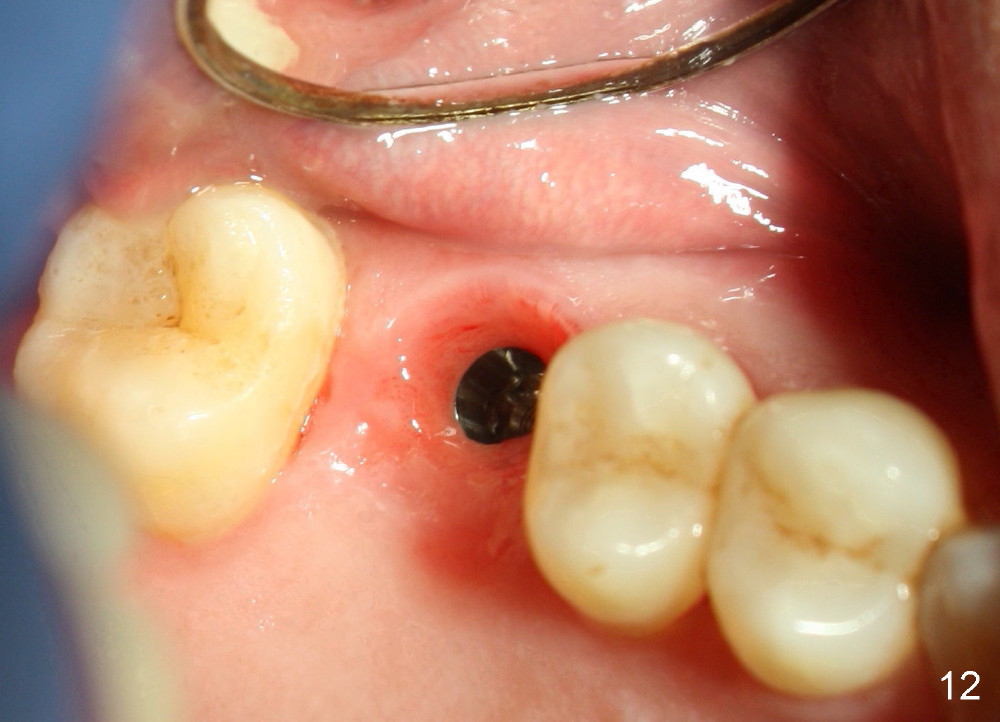

The tooth #3 has a crack line (Fig.1 ^). The septum (Fig.2 S) looks like an inverted pyramid (Fig.3), coronal part being pointed, whereas the apical broad. The shape of the septum is not so favorable to placement of tapered implant. Osteotomy starts with 1.5 mm pilot drill in the middle of the septum, followed by round tapered osteotomes 2 and 3 mm. The osteotomy begins to deviate into the mesiobuccal socket. The same osteotomes are used to re-direct the osteotomy palatally, followed by tapered drills, trying to move osteotomy palatally. A 4.5x17 mm tap is inserted with stability (Fig.4). Following using 5x17 mm tap at the depth of 12 mm, a 5.3x12 mm bone-level implant is placed ~ 1.5 mm below the crest, 1.5 mm above the septum (Fig.5). Demineralized cortical human allograft is placed in the remaining sockets and around the most coronal aspect of the implant (with a small piece of gauze placed in the implant well). After removal of the gauze, a piece of collagen membrane is pierced and carried by a 8.2x4/3 mm healing abutment and fixed in place (Fig.6 M). The periphery of the membrane is tucked underneath the gingiva. The wound is covered by perio dressing. The patient returns to clinic for follow up 8 days postop. There is no discomfort. In order to protect the collagen membrane (Fig.6), the perio dressing is intentionally not removed (Fig.7). Two weeks postop, the patient remains asymptomatic. After perio dressing removal, the membrane appears to have been resorbed (Fig.8 as compared to Fig.6). The bone graft (B), although exposed, remains in place and condensed, surrounded by healing healthy gingiva (*). The patient returns 2.5 months postop. The implant appears to osteointegrate (Fig.9, as compared to Fig.5). The buccal (Fig.10) and palatal (Fig.11) gingiva adapts to the healing abutment. When the healing abutment is removed for restoration 3 months postop, the gingiva looks healthy (Fig.12). A cemented abutment (5.8x4(2) mm) is placed; a crown is fabricated (Fig.13). The patient returns for recall 5 months post cementation. He reports food impaction distal to the crown. The gap mesial to the implant has closed (Fig.14).